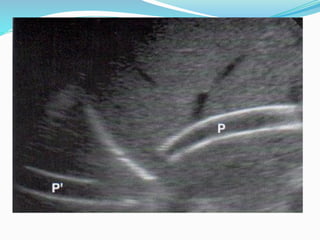

ARTEFACTO POR IMAGEN EN ESPEJO

Las “imágenes fantasmas” aparecen por detrás de

reflectores fuertes porque altera la vía del haz y duplica

su tiempo de tránsito. El tejido hepático localizado

debajo del reflector fuerte del diafragma se proyecta a

una localización supradiafragmática en la zona

pulmonar basal (seudoeco) . Puede producir errores de

interpretación.

A veces el parénquima normal del hígado y el bazo

imita un derrame pleural, descartable por exámenes

en otra posición u obteniendo imágenes desde la cara

posterior.

IMAGEN EN ESPEJO

hemangioma hepático cerca del diafragma que da una imagen igual extradiafragmática que es la imagen en

espejo